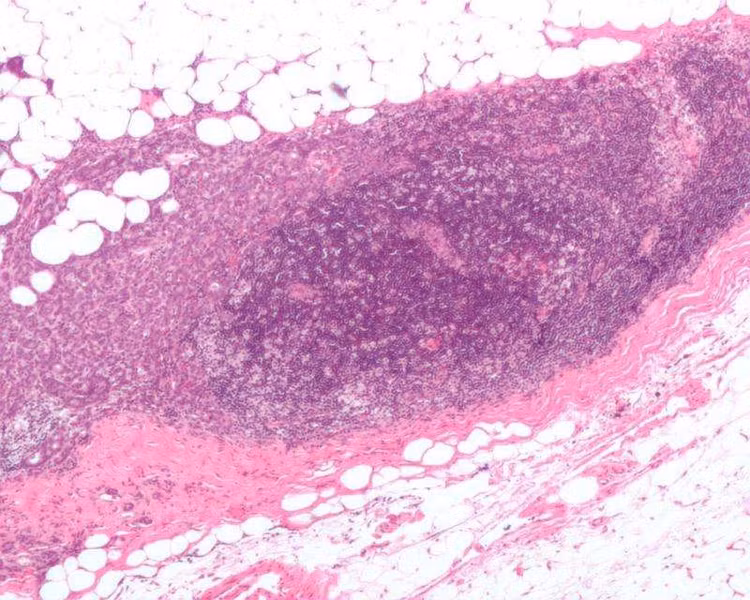

Ảnh hiển vi một hạch bạch huyết bị ung thư biểu mô vú xâm lấn, với phần mở rộng của khối u ra ngoài hạch bạch huyết. Ảnh: Nephron / Wikipedia.